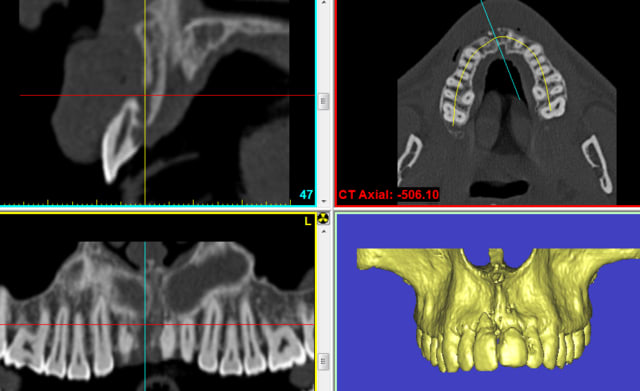

Puisque l'adan a réussi une joli planif avec le "be open plan", et me l'a envoyé dans la dropbox

je mets sur son cas,une video du principe de réalisation d'un guide

Bien sûr ce guide serait inutilisable pour beaucoup de raisons mais c'est ainsi que je fais mes guides en quelques minutes

Et voila première pose après planification et impression d'un petit guide chirurgical . Pour un debutant qui pose de facon occasionnel c'est très sécurisant ! j'ai pu mettre un implant plus long sans etre stressé par la presence du sinus et un axe qui ma satisfait pleinement . A renouveler !! et encore merci à beotien pour tous ses conseils et aux autres qui ont participé à cette aventure

voici quelques images que j'ai reçu, de 3 confrères donc de 3 radiologues différents.

pouvez vous me dire ce qui ne va pas!

vous demandez des scans aux radiologues mais si vous voulez les utiliser il faut leur donner des indications précises

N'oubliez jamais qu'ils ne sont pas dentistes!